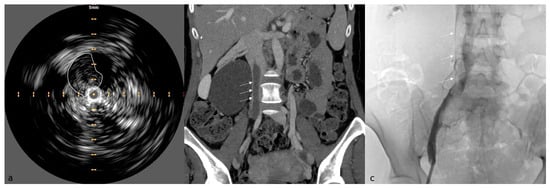

6. IVUS in Venous Stenting Procedure